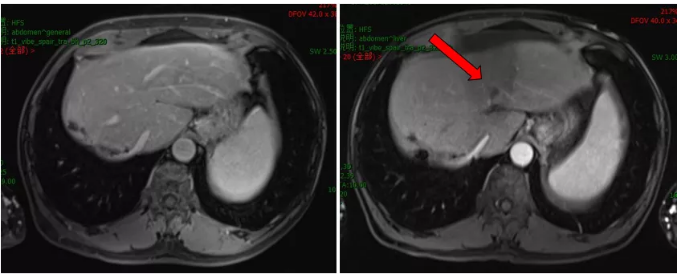

化疗前后病灶变化情况

治疗前后病灶变化情况